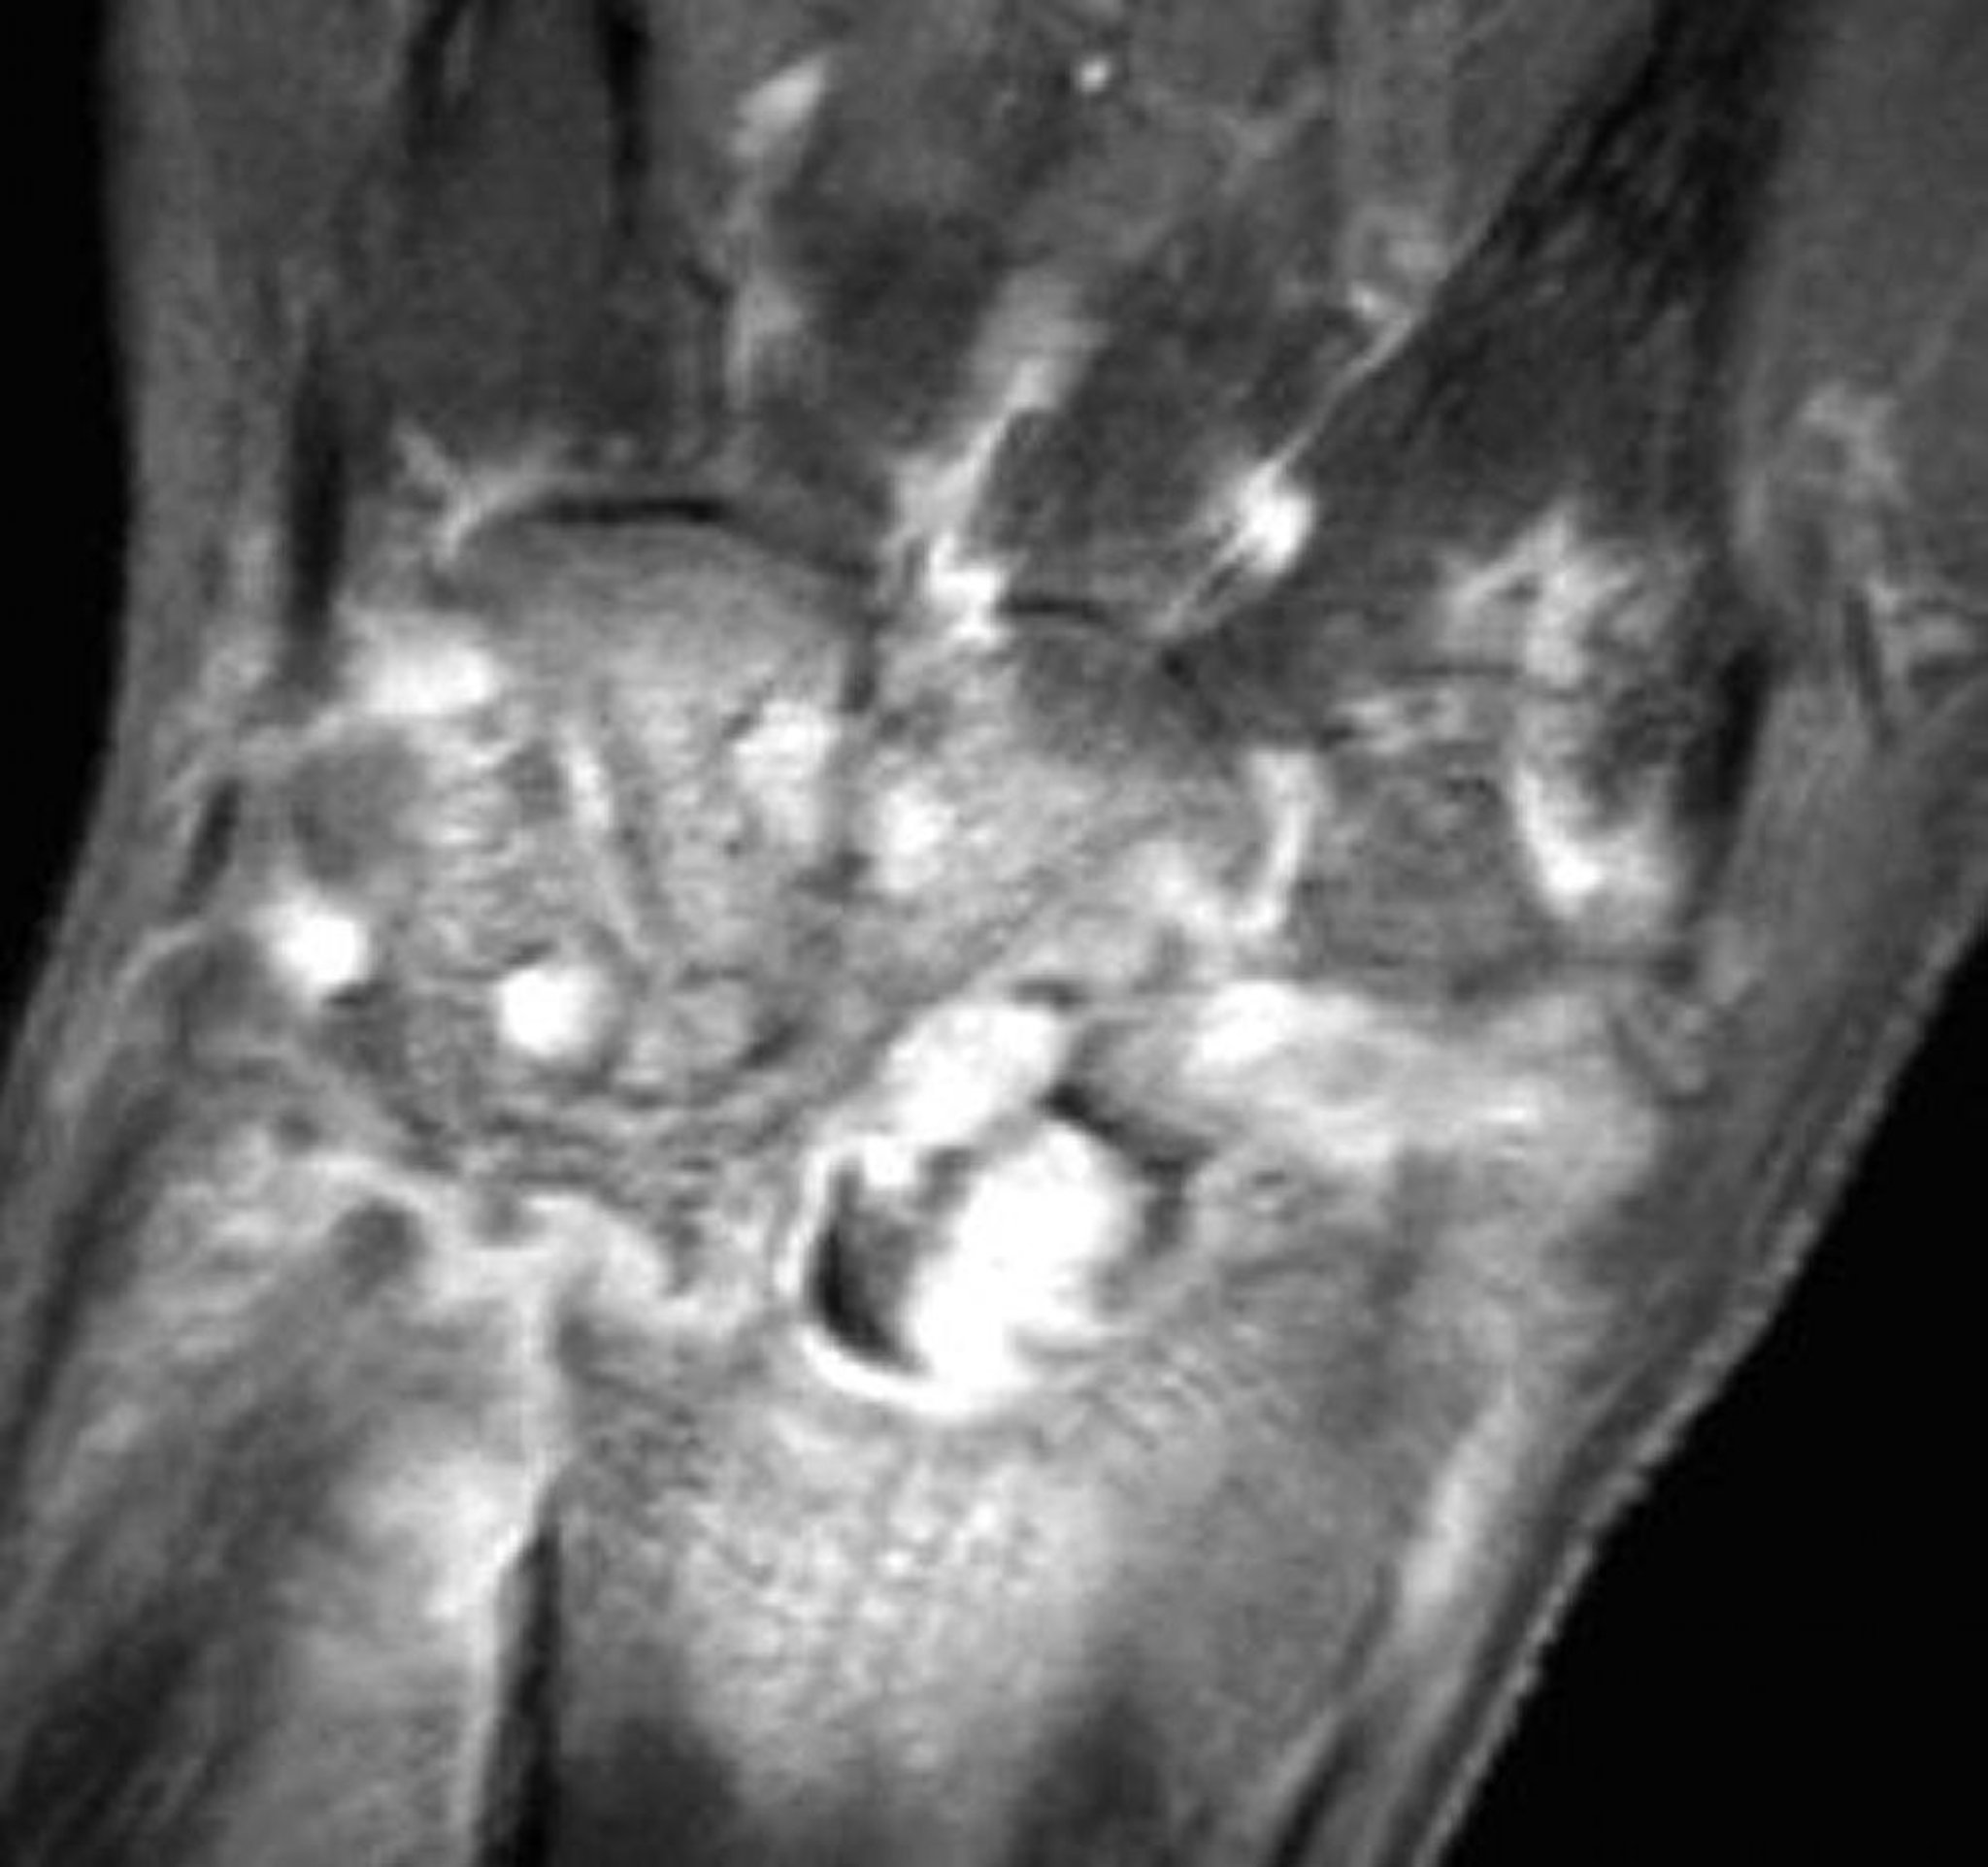

IRM dans l'arthrite gonococcique du poignet

Cette IRM avec réduction de la graisse coronale pondérée en T1 avec gadolinium d'un poignet atteint d'arthrite septique gonococcique montre une prise de contraste synoviale et des érosions diffuses.